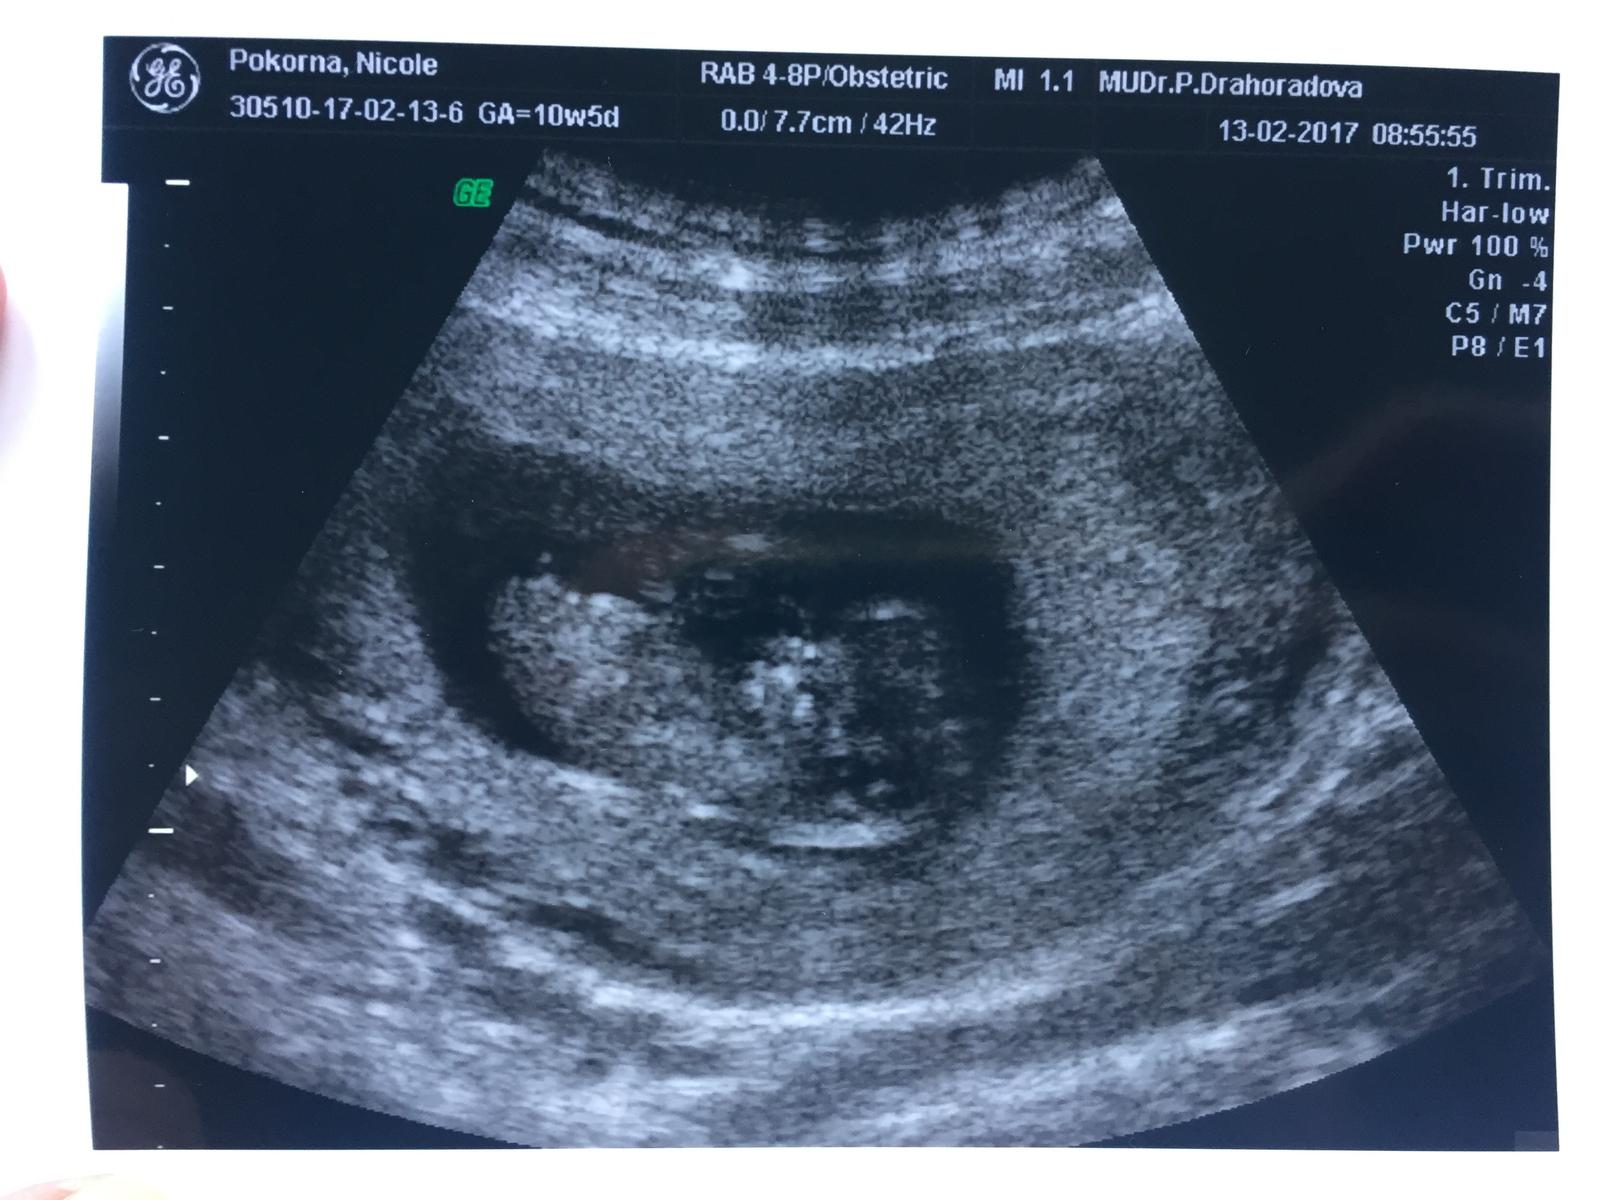

Je to holčička nebo chlapeček? Foto ultrazvuku

Nedávno jsme sem dávala fotku z utz, tak hlásím, ze vedle mě leží osmidenni chlapeček 🙂

@tinka2017 ahoj Tinko, my jsme měli úplně tu stejnou fotku a narodil se nám 100% chlapeček. Hlavně ať je miminko zdravé, není nic důležitějšího 🙂

Těžko říct nejsem odborník, ale osobně si myslím že chlapeček.

Kluk jak bud. Ten bílý trojúhelní je pindík co se vznásí v plodovce :D